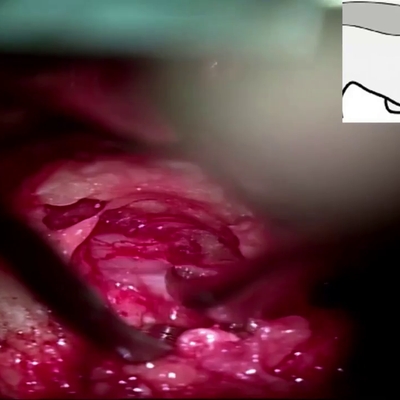

Click on an image below to view more info.